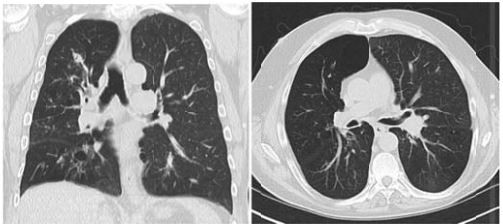

Mulher, 51 anos, caminhada para investigação de pneumonia de repetição. Relata crises compatíveis com asma brônquica, com tosse persistente. Há oito meses apresentou sintomas de dor pleurítica no lado esquerdo, tosse e discreta expectoração, tratada com antibióticos. Há seis meses, radiograma de tórax mostrou infiltrado peri-hilar no pulmão direito e sinais de broqictasia central, tratava com lavofloxacina por 21 dias. Após dois meses, novo estudo radiológico mostrava que o infiltrado permanecia . Antecedentes pessoais: alergia a vitamina B, otite crônica supurativa e hipotireoidismo subclínico. Pneumonia de pulmão D aos 29 anos. Nega tabagismo ou etilismo. Exame físico: sem alterações. Exames laboratoriais: Hemograma: hemoglobina 11 g/dL; hematócrito 35%; leucócitos 9.300/mm³ (60% segmentados, 20 % linfócitos, 7% monócitos, 13% eosinófilos); VHS 53mm. Imunoglobulinas: total 146 mg/dL; IgA 134mg/dL; IgM 153mg/dL; IgG 817mg/dL. Sub-classes de IgG: IgG3 no limite inferior de normalidade. Espirometria: CVF 3.700mL (116%), VEF1 2.600mL (103%), índice de tiffenau de 70%. Tomografia computadorizada de tórax:

A hipótese diagnostica e tratamento são: